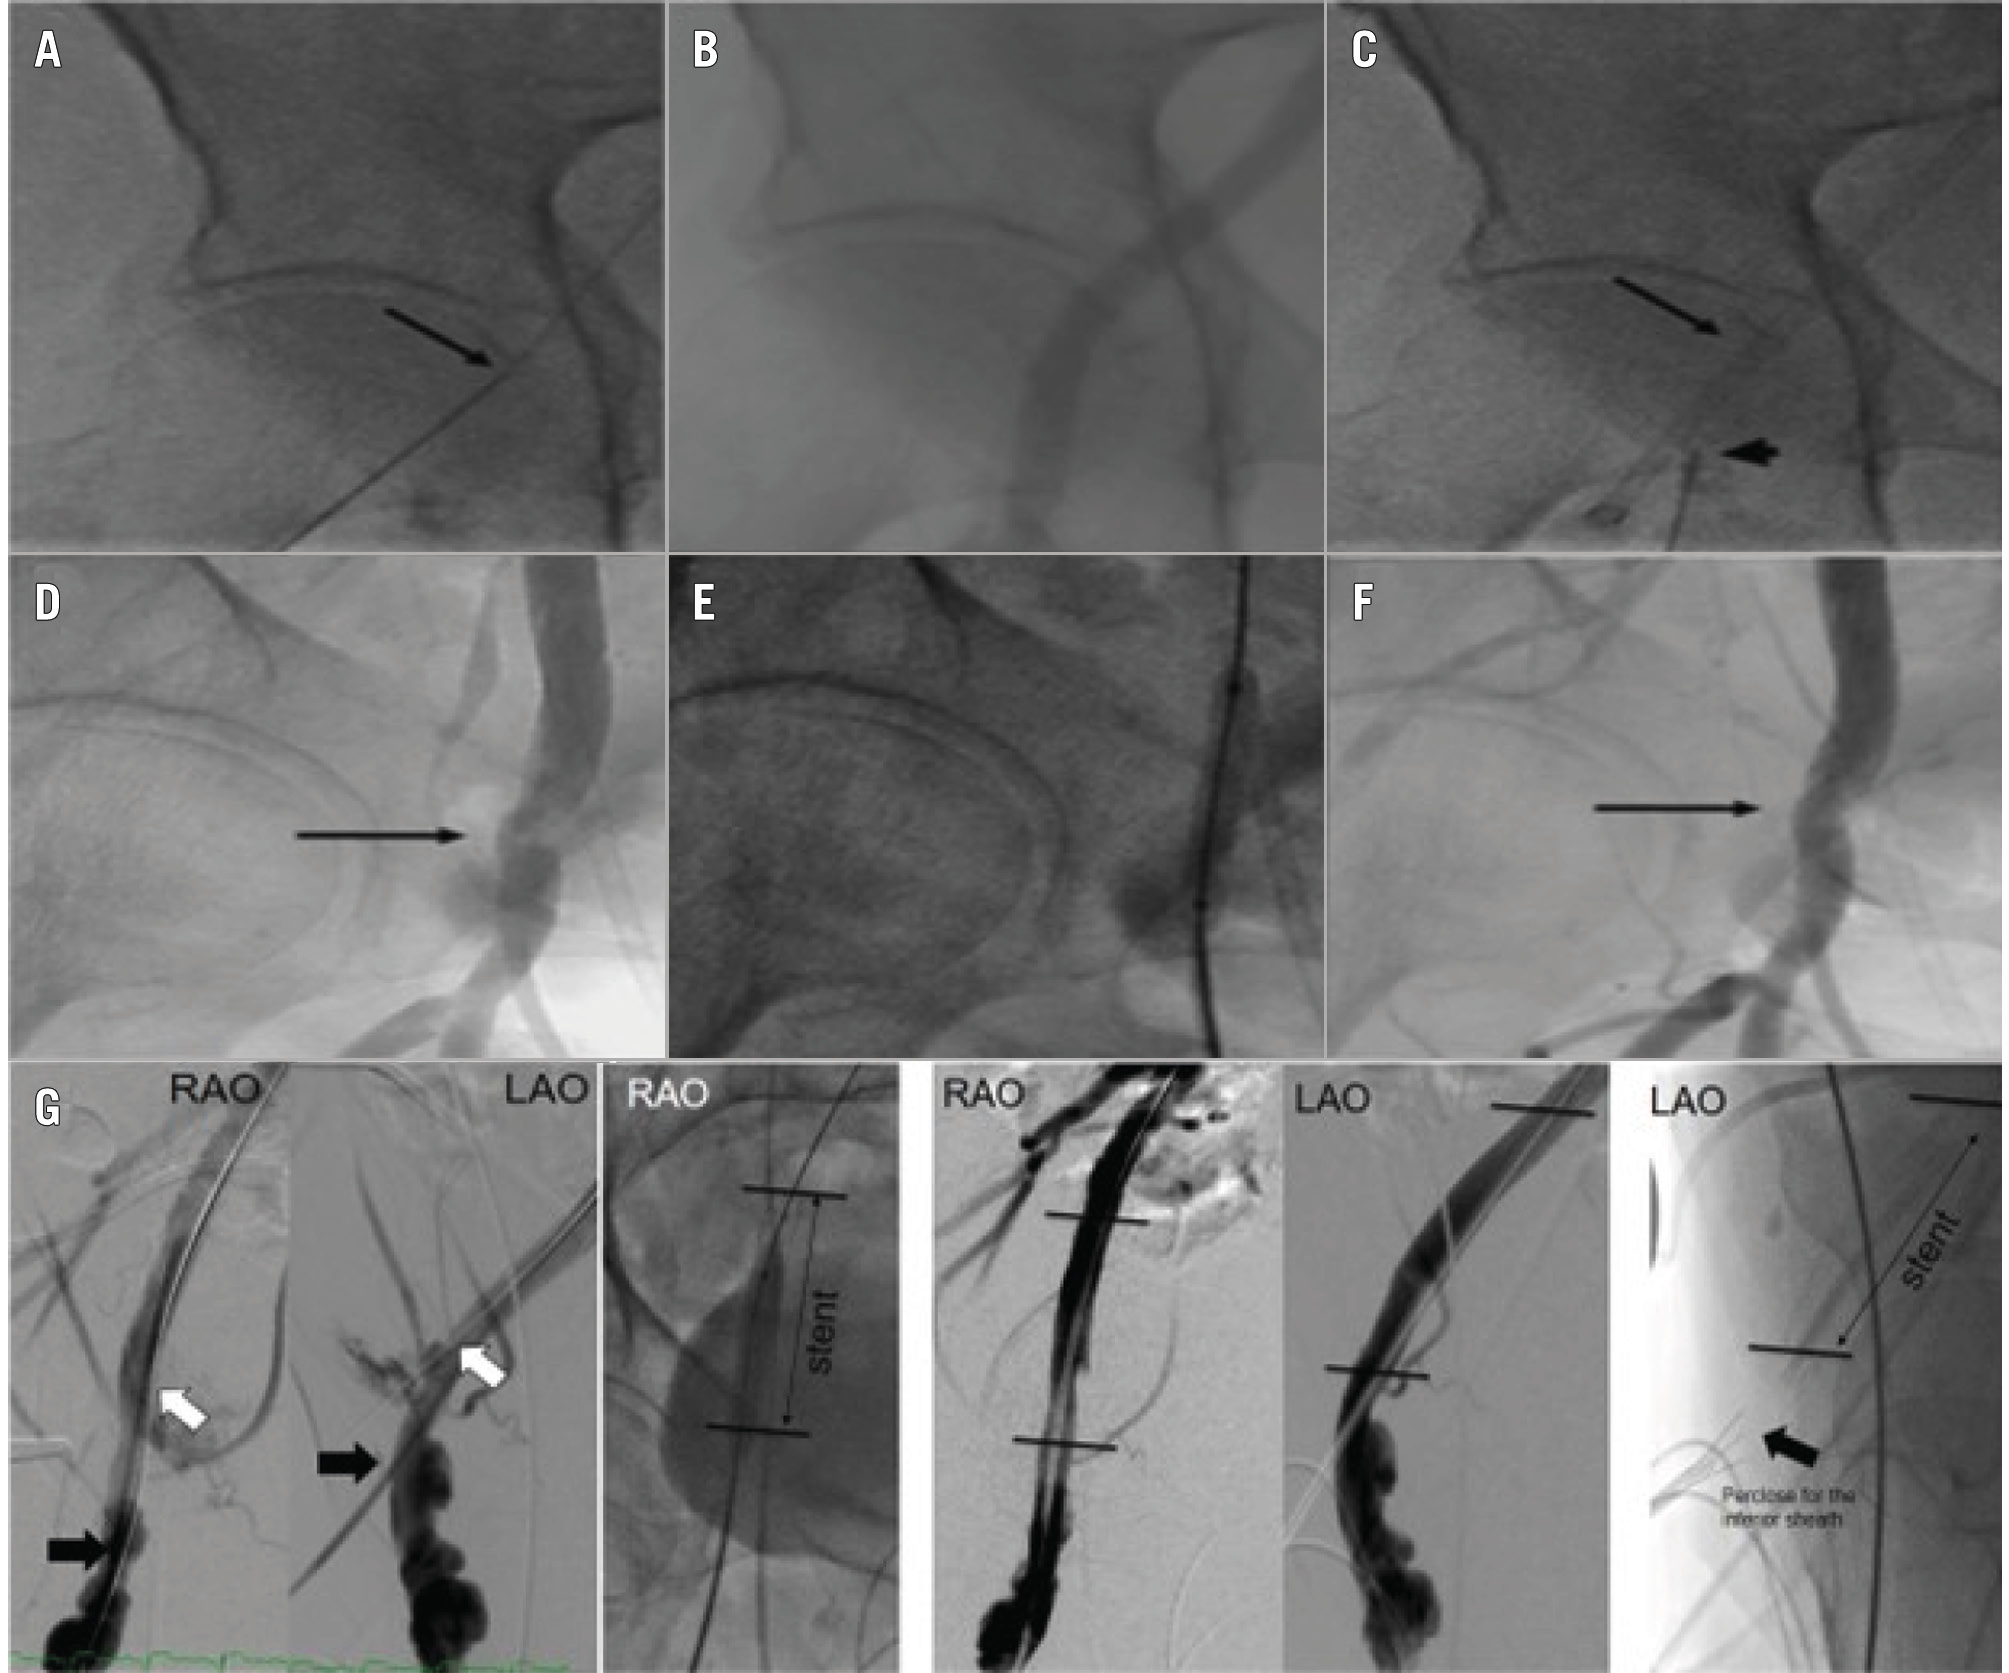

At our institution, unilateral sheath insertion has become the preferred access strategy, with placement of a 5 Fr sheath for aortic root procedures and femoral completion angiography 2-3 cm inferior to the TAVI delivery sheath access point49. With the use of a unilateral access site, complications can be easily managed as this inferior sheath is already across the delivery sheath access point, making balloon dilatation and/or stent placement straightforward in comparison to crossover techniques from the contralateral femoral artery or via the wrist (Figure 4). Furthermore, alternative access TAVI can be utilised in case of a challenging common femoral artery access.

Figure 4. Peripheral intervention via unilateral arterial access. A) Proximal RFA access site for delivery sheath (arrow). B) RFA angiogram. C) Proximal RFA sheath (arrow) and inferior RFA access site (arrowhead). D) Completion angiogram via inferior sheath shows delivery sheath site stenosis (arrow). E) Angioplasty via inferior sheath. F) Resolution of RFA delivery site stenosis (arrow). G) A separate patient with iliofemoral dissection who was successfully treated with a stent via unilateral access. LAO: left anterior oblique; RAO: right anterior oblique; RFA: right femoral artery